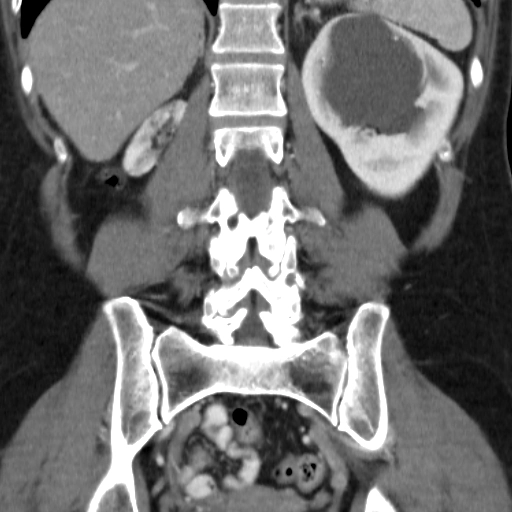

Hệ bài tiết đôi (Duplex collecting system)